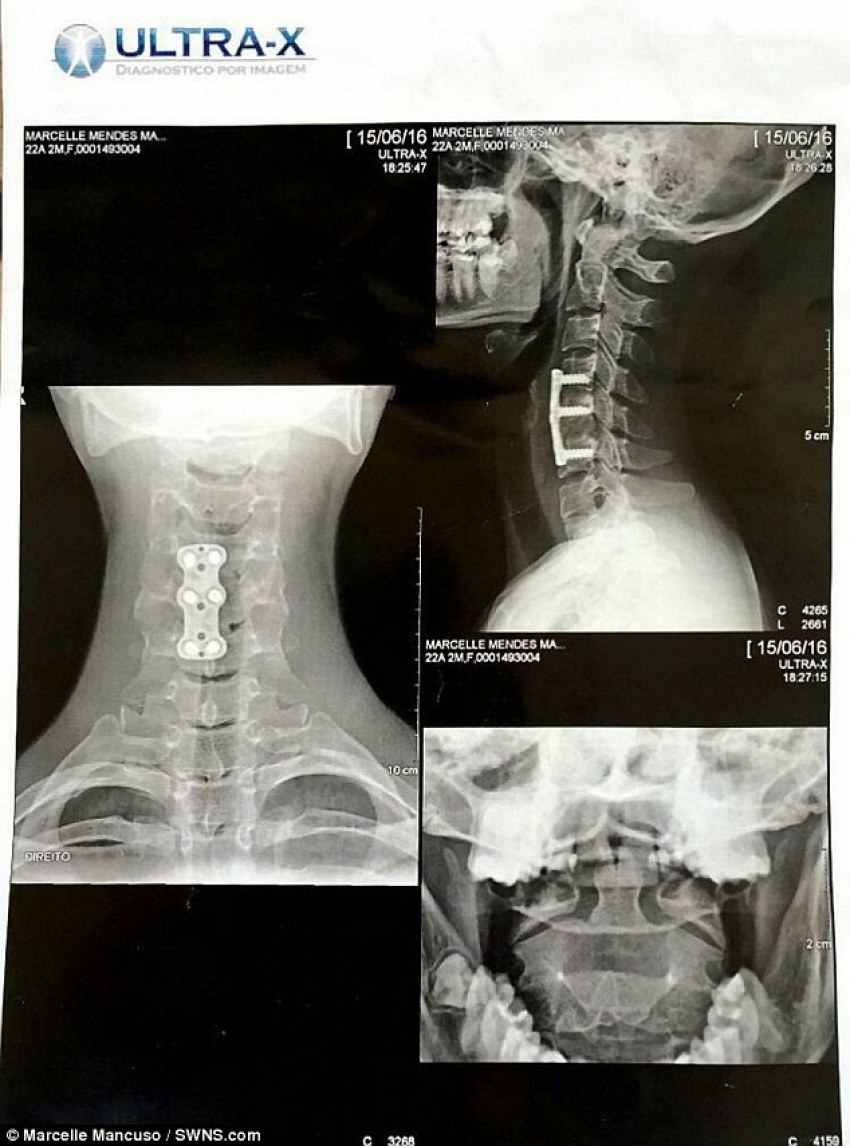

After being rushed to the hospital, Mancuso was told she had broken the fifth vertebrae in the neck section of her spine, knocked another one out of place, and squashed a third, compressing her spinal cord.

Doctors performed emergency surgery and fitted her with a titanium plate held by six screws into her spine, but warned her she may never regain feeling in her arms and legs.